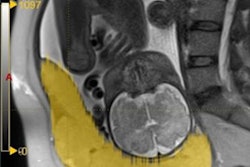

Axial T2-weighted single-shot fast spin-echo MR image shows an irregular outer uterine contour with discontinuity of the T2-hypointense myometrial layer in the anterior uterine segment. All images courtesy of Dr. Leonor Alamo.Their retrospective study included 25 pregnant women (mean age 35.16) -- 12 with histopathologically proven placental invasion and 13 without to act as a control -- who were investigated by prenatal MRI without IV contrast at three hospitals using three different 1.5-tesla MRI units (Magnetom Symphony, Siemens Healthcare; Intera, Philips Healthcare; Signa, GE Healthcare). The women underwent MR imaging between June 2007 and December 2009 after obstetrician referral for suspected placental invasion upon standard pregnancy ultrasound exams. The MRI protocols were similar and included T1-weighted volume interpolated gradient-echo MR sequences in the sagittal and axial plane, single-shot fast spin-echo T2-weighted MR sequences, and true fast imaging with steady-state precession in the axial, sagittal, and coronal planes.

Sagittal T2-weighted single-shot fast spin-echo MR images show the placenta previa and evidence focal bulgings of the anterior uterine wall. The signal intensity of the placenta is heterogeneous, with presence of T2-hypointense placental bands. Observe the discontinuity of the myometrial layer, extending beyond the uterine serosa.The kappa values for interobserver agreement for detecting placental invasion were substantial (0.64) for seniors and moderate (0.41) for juniors. Seniors detected placental invasion and depth of infiltration with significantly higher diagnostic accuracy than juniors.